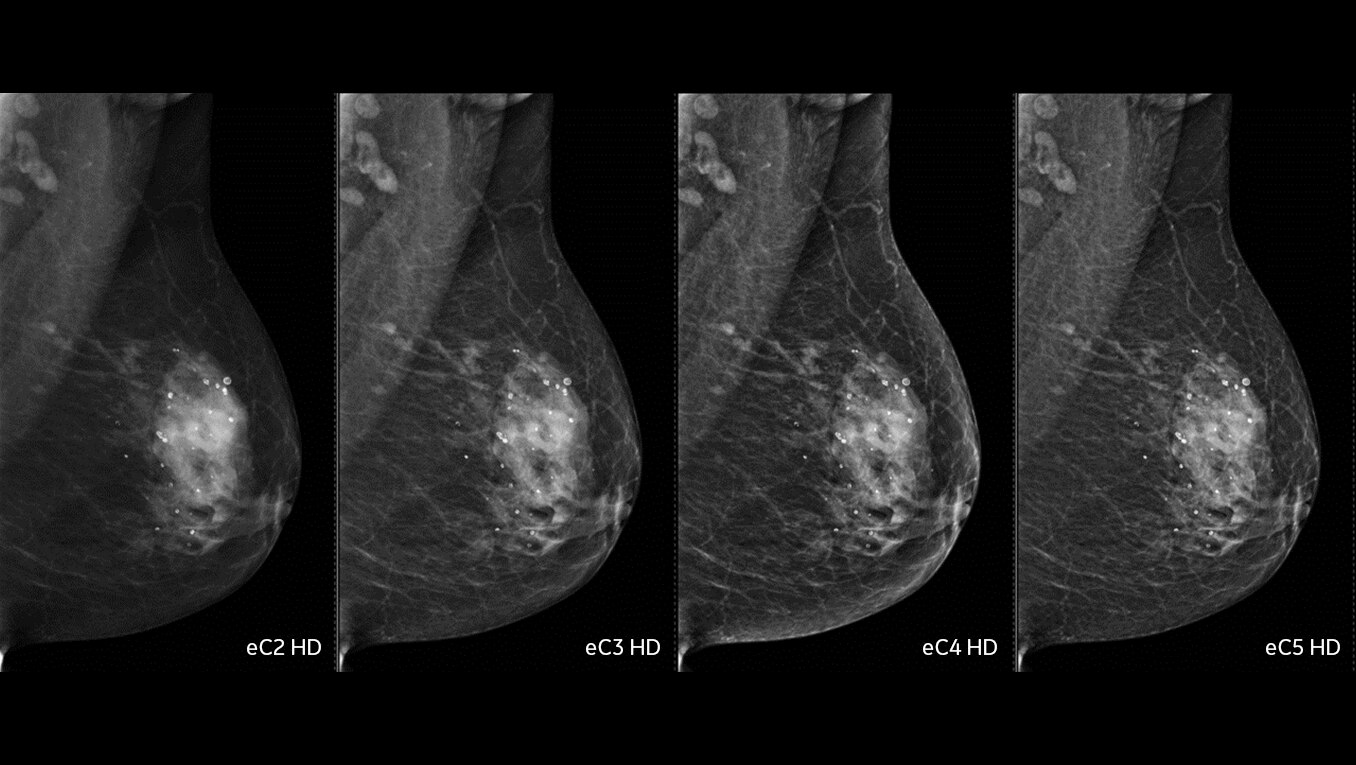

Reconstrução de imagens de RM com AIR™ Recon DL

Imagens simplesmente melhores